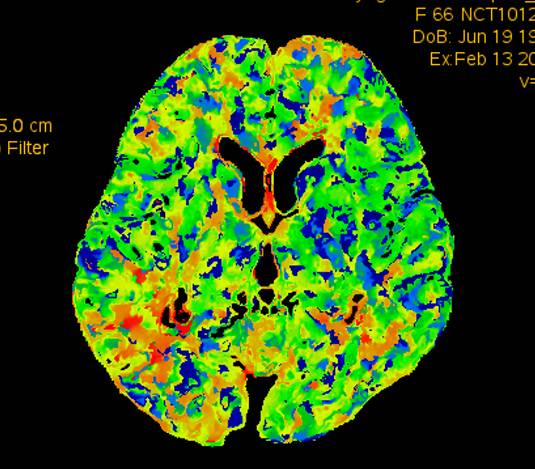

术前CTP示:右侧大脑半球灌注较差。

术后2个月患者未再诉右眼黑曚。复查CTP示:颅内灌注明显改善。

术前灌注成像,右侧大脑半球灌注较差。